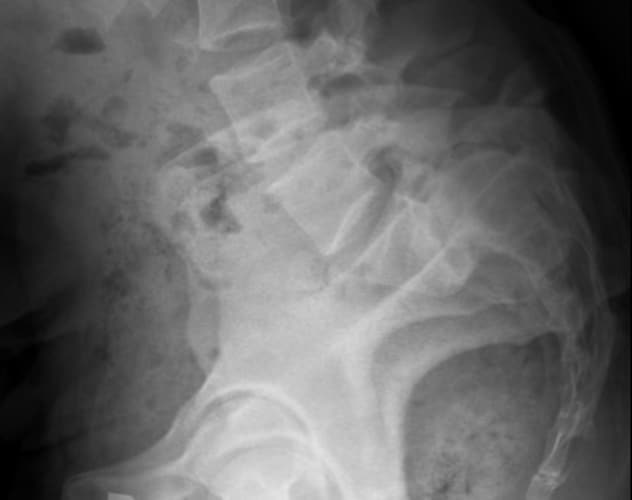

Preoperative X-ray shows severe spinal curvature in a 30-year-old woman with high-grade congenital spondylolisthesis. She presented at Mayo Clinic with intractable back pain and leg pain, which did not resolve with nonoperative treatments.